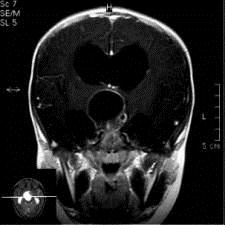

问题 病历摘要:??患者女性,6岁,半年来感觉视力模糊,近10天出现反复头痛,间有恶心呕吐,精神转差,查体:神志清楚,身高90cm,体重25Kg,血压90/55mmHg,右眼视力4.6,左眼视力4.8,双侧视乳头水肿,颈软,伸舌居中,四肢肌张力正常,肌力5级,双侧Babinski征(-)。 患者术后第三天,病情加重,检查生化,血钠145mmol/l,尿比重1.010g/l,复查头部CT,发现右侧大脑中动脉供血区域密度减低,右侧脑室受压,蛛网膜下腔、脑室内少量积血,中线有移位,环池显示欠清,这时应采取的治疗措施有?

选项 A.甘露醇125ml快速静滴 B.尼膜地平静滴舒张血管 C.右侧额颞开颅去骨瓣减压术 D.低分子肝素皮下注射 E.右侧额颞开颅颞叶切除术 F.侧脑室穿刺外引流术 G.右侧额颞开颅去骨瓣+颞叶切除术